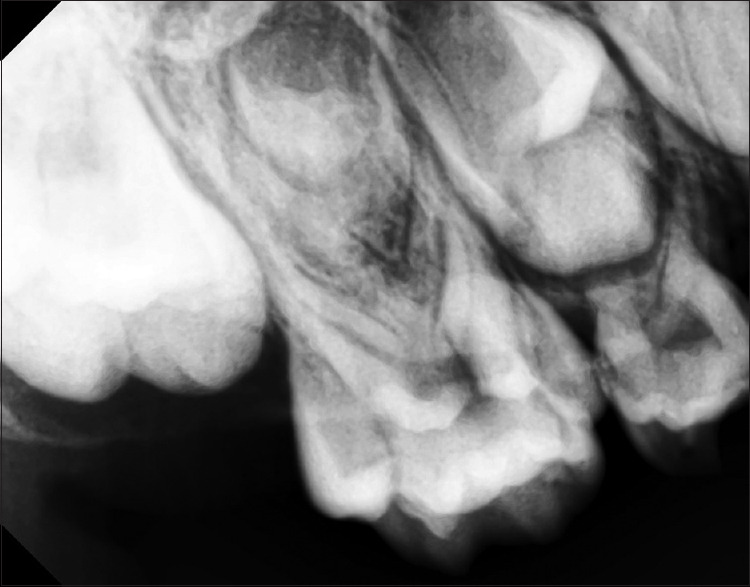

A 6-year-old female patient reported to the Department of Pedodontics and Preventive Dentistry for the treatment of her carious teeth. Family history and medical history were noncontributory with no signs of any syndrome. On intraoral examination, there was no pain or swelling associated with the tooth and no abnormality of soft tissues was noticed. The intraoral examination revealed that the patient was in a primary dentition stage with poor oral hygiene. Detailed dental examination resulted in the incidental clinical findings of supernumerary cusp on the occlusal surface of the maxillary right second primary molar with a central cusp and caries extending into the pit and fissures [Figures 1 and 2]. On clinical examination, the patient had no relevant extraoral findings. The intraoral periapical radiograph also shows the presence of multiple cusps with pulpal extensions [Figure 3]. The occlusal pit and fissure caries of 55 were carefully removed to prepare a conservative cavity with the help of round bur using airotor, followed by excavation of soft dental caries using spoon excavator. Due to favorable properties of glass ionomer cement such as chemical bonding with the tooth structure and fluoride-releasing capacity, the prepared tooth was restored using glass ionomer cement.

Figure 3.

Radiovisiography of ten-cusped primary maxillary right second molar with pulpal extensions into the cusps